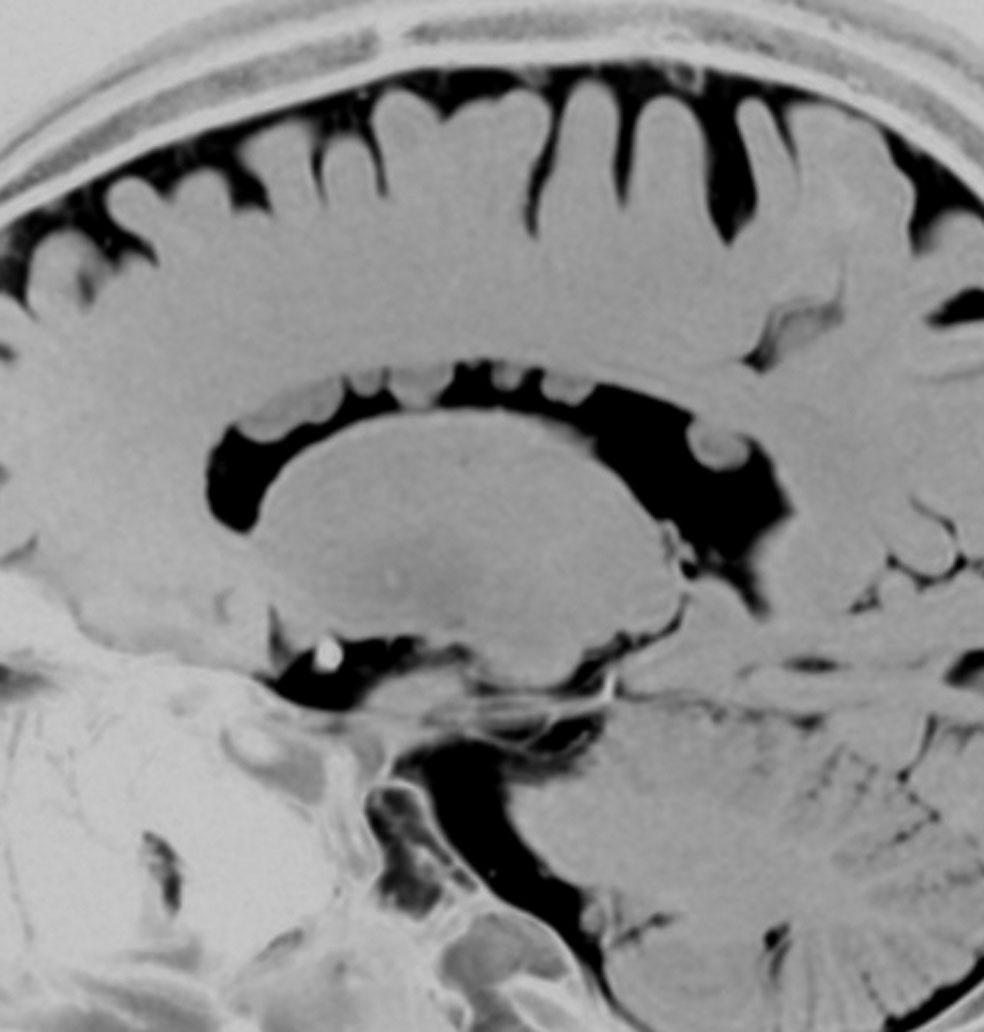

結節性硬化症 TSに見られる多発性上衣下結節 subependymal nodules

32歳で初めて睡眠時てんかん発症した患者さんのものです。側脳室壁だけに無数の上衣下結節がありますが,治療の必要はありません。SEGAではありません。